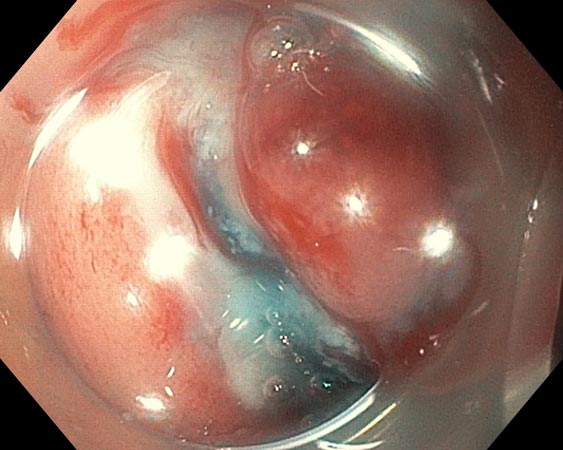

До проведения ESD выполняли эндоскопическую оценку образований в соответствии с Парижской классификацией, классификацией ямочного рисунка (Kudo S., 1996), сосудистого рисунка (Sano Y., 2010). Пациентам с подслизистыми образованиями выполняли эндосонографию прямой кишки и биопсию с иммуногистохимическим исследованием. В ходе эндосонографии выявлены гипоэхогенные образования размерами 0,6 и 0,8 см с интактным мышечным слоем и отсутствием увеличенных регионарных лимфатических узлов (рис. 1, 2).

Рис. 1. Подслизистое новообразование прямой кишки

Рис. 2. Эндосонограмма подслизистого новообразования прямой кишки